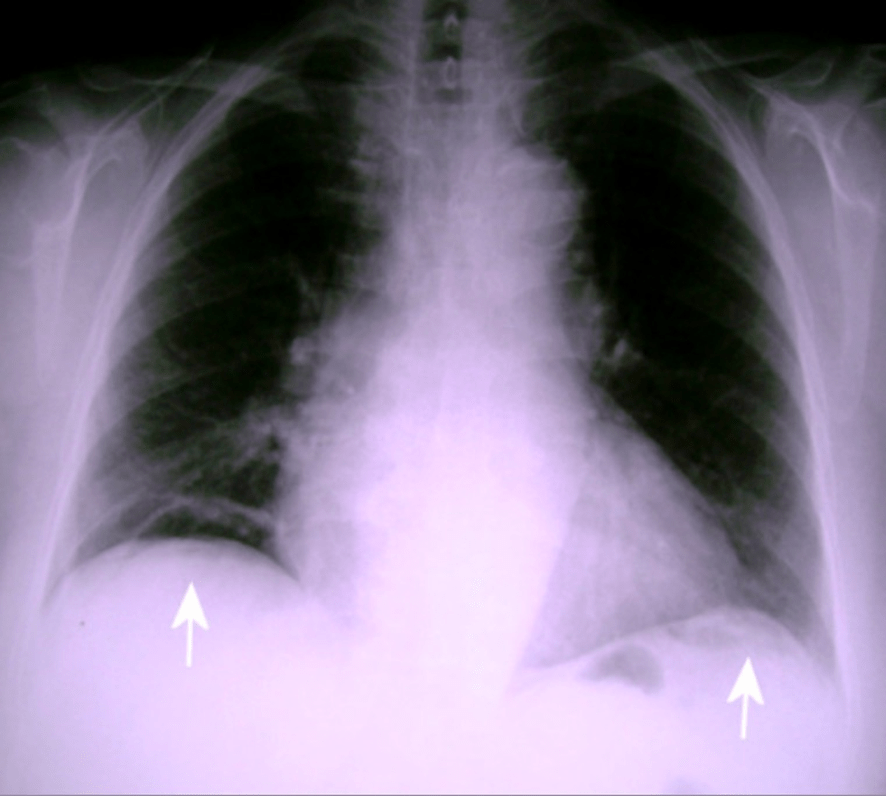

Aun que presentamos radiografia de Torax para ilustrar la patología, es normalmente con abdomen en bipedestación como se localiza este hallazgo.

A. Radiografía anteroposterior de tórax mostrando la presencia de neumoperitoneo a ambos lados diafragmáticos (flechas). B.Radiografía lateral de tórax mostrando el neumoperitoneo (flecha). C-D: Radiografía anteroposterior y lateral respectivamente, realizadas al mes tras la intervención, en las que se comprueba la resolución del neumoperitoneo (flechas), con una mínima elevación del hemidiafragma derecho (flecha), en ausencia de derrames pleurales a nivel bilateral. Los alambres esternales son patentes así como la visualización de las prótesis valvular aórtica mecánica y mitral biológica.